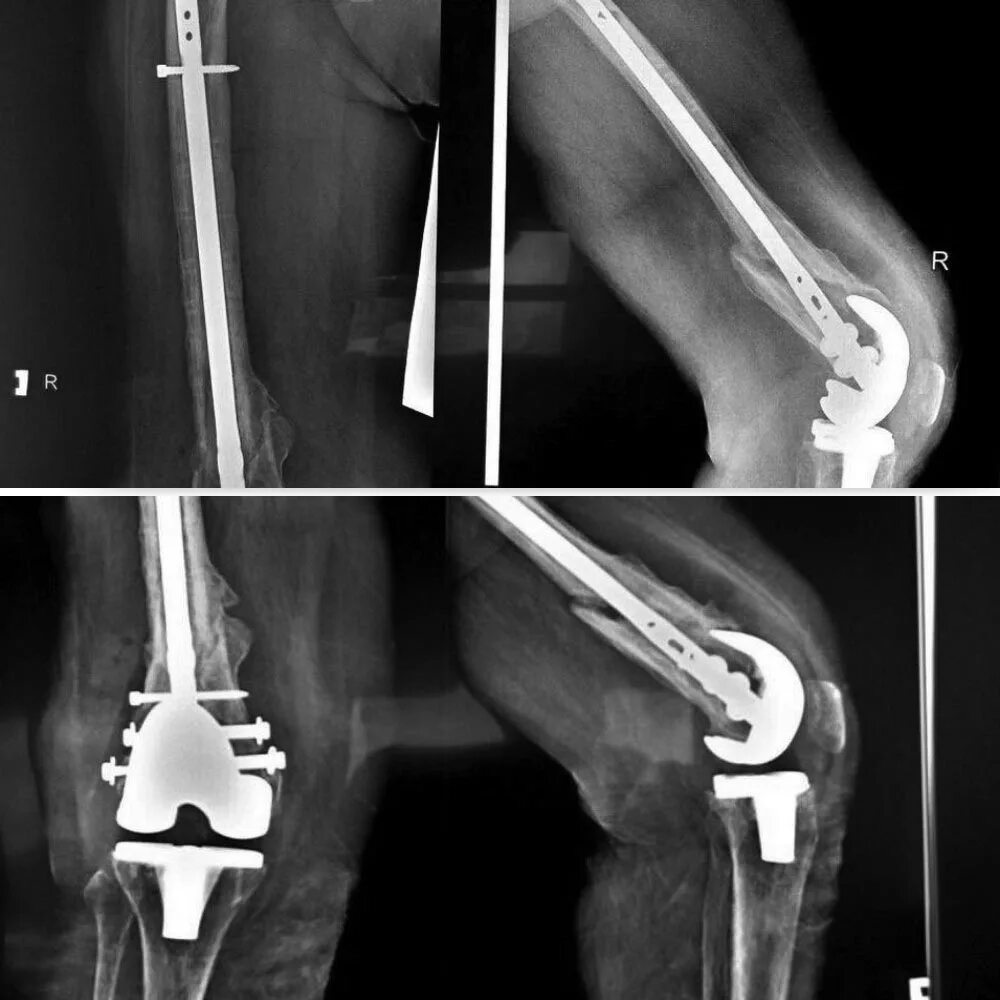

Операция эндопротезирование коленного